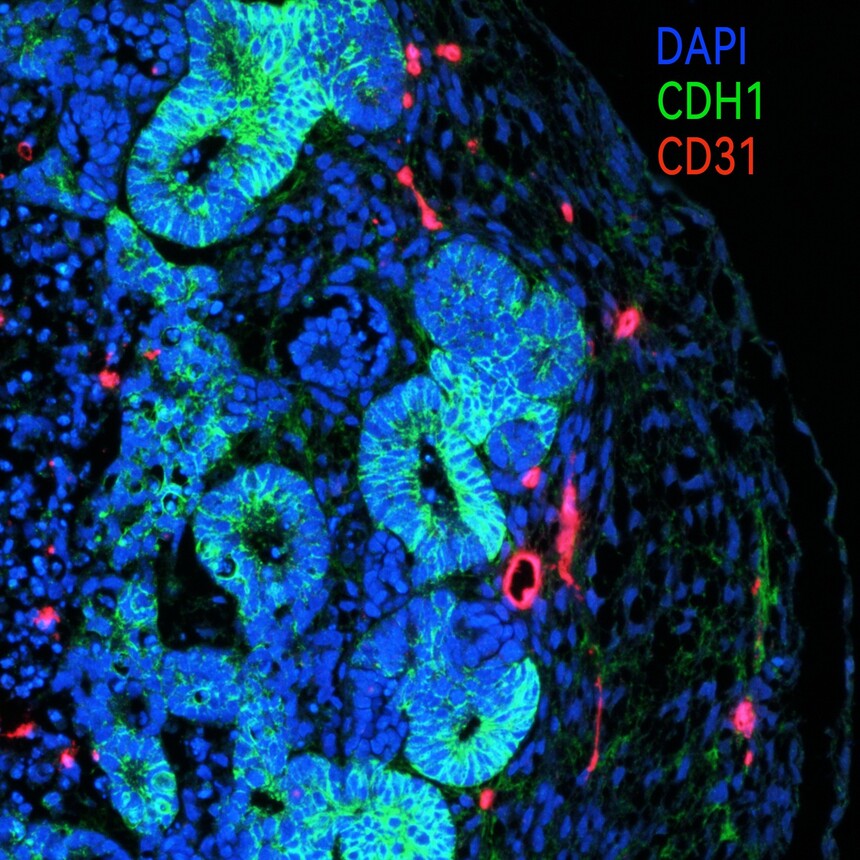

诱导形态示例图:

产品引用 Qian Z, Yang D, Li Y, Dong R, Da J, Chen Y, Zha Y. Analysis of high glucose injury using human induced pluripotent stem cell-derived kidney organoids. BMC Nephrol. 2026 Jan 8. doi: 10.1186/s12882-025-04566-6. Epub ahead of print. PMID: 41507800. 人肾类器官分化试剂盒 仅用于科学研究 产品信息 产品名称:人肾类器官分化试剂盒 货号:RC200134 批号:见包装 试剂清单:

存储与有效期: 组分1、2、3、4于-20至-80 ℃避光保存,必须避免反复冻融;首次完全解冻后可以按使用量进行分装,置于-20至-80 ℃长期保存;2-8 ℃条件下,稳定储存2周。组分5于2-8℃避光保存,有效期1年。 适用范围: 本试剂盒适用于人多能干细胞(胚胎干细胞、诱导多能干细胞)定向肾系细胞分化,同时进行立体培养,形成血管化肾类器官。 产品介绍 类器官与悬浮培养是当前再生医学研究与应用的前沿,是未来再生医学与组织工程发展的趋势。为适应日益发展的科研需求,并为生命科学尤其是再生医学研究的需要,开发优化了相关产品,可以为科研工作者提供稳定的研究平台,以助力研究的时效性和经济性。该产品设计同时考虑再生医学临床前研究的需求,可以为研究人员提供大量稳定的种子细胞,加速应用后期技术的研发。 本产品无血清、成分明确、含有细胞保护因子,适合于人多能干细胞向血管化肾类器官的诱导。 操作方法 实验准备 u 完全培养基准备: 组分1-4(S1、S2、S3、S4)均为完全培养基:2-8℃解冻。完全融化后轻轻摇匀,可以按照实际使用量分装。分装后立即存储于-20至-80 ℃,避免反复冻融。 注意:2-8℃冰箱过夜,切不可置于37℃水浴剧烈解冻,解冻后请务必充分混匀,以保证培养基成分的均匀度。冷冻组分解冻时会有絮状沉淀或结晶,每次使用前混合均匀使用即可,不影响使用效果。 u 自备试剂耗材: l 多能干细胞完全培养基(推荐使用mTesR1培养系统) l 多能干细胞消化液(Accutase等) l 基质胶 l 贴壁细胞培养板 l 低吸附细胞培养板 l Rock抑制剂(Y27632) l 细胞固定液(2-4%中性多聚甲醛) 操作方法 1. S1阶段:诱导第0天,人多能干细胞生长至约60%汇合开始血管化的肾类器官诱导分化,要求人多能干细胞克隆形态良好。用基础培养基(RC200134-5)每孔2-3 ml洗细胞2次,加入S1完全培养基每孔2 ml,每天换液,连续4天。该阶段为原条诱导阶段(primitive streak)。有部分细胞死亡为正常现象。 注意:本操作方案以六孔板为例,若使用其他器皿可以根据需要自行调整方案。调整方案时建议以细胞密度为稳定因素。细胞培养箱条件为37℃、5% CO2、饱和湿度。所有培养基在使用前必须进行室温复温。这些注意事项同样适用于以下步骤。 注意:起始的多能干细胞(ES、iPSC)对后续诱导成功非常关键,请务必保证诱导时多能干细胞生长状态良好,50-60%汇合(参考诱导形态示例图)。该阶段诱导过程中有部分细胞死亡为正常现象。 2. S2阶段:诱导第5天,用基础培养基每孔2-3 ml轻柔洗细胞2次,加入S2完全培养基每孔2 ml,每天换液,连续3天。该阶段为肾中胚层特化阶段(kidney mesodermal specialization)。 注意:移液枪吹打细胞时务必轻柔,切不可产生大量气泡,本试剂盒全程均需注意此问题。 3. S3阶段:诱导第8天,用基础培养基每孔2-3 ml轻柔洗细胞2次,加入S3完全培养基每孔2 ml,每天换液,连续4天。该阶段为肾祖细胞阶段(nephronic progenitor cells)。 4. S4阶段:诱导第12天,用DPBS每孔2-3 ml轻柔洗细胞2次,加入适量(每孔1 ml)消化液Accutase(Gibco,货号A1110501),同时加入终浓度为10 μM的Rock抑制剂(Y27632)以提高细胞存活率。细胞消化约3-6分钟,待细胞易吹下即加入适量(每孔1-2 ml)S4完全培养基终止消化。收集细胞悬液到离心管中,800 转/分离心5分钟,弃上清;用适量S4完全培养基重悬细胞,同时加入终浓度为10 μM的Rock抑制剂(Y27632)。细胞接种于低黏附的培养器皿,6孔板一个孔消化的细胞接种于1个低黏附6孔板的一个孔,S4完全培养基加入量为每孔2-3 ml,每天用S4完全培养基每孔2-3 ml换液(不需添加Rock抑制剂)。培养过程中可通过低速离心的方式去除死细胞。若细胞团块过大,可以用枪头轻柔吹打至均一大小,继续培养至第24-26天。该阶段为相对成熟的阶段(maturation of kidney cells)。 注意:低速离心的方法为,收集细胞悬液,置于离心管中,建议200转/分,离心3-5分钟,弃上清。死细胞不会沉底,弃上清即可去除死细胞。细胞沉淀用完全培养基重悬,继续培养。 注意:S4阶段诱导过夜后细胞便会聚团成球(参考诱导形态示例图),若此时成球不明显,则后续成功的可能性很小,请注意根据形态示例图判断。 注意:继续培养过程中,若细胞团数量过多,可适当分到其他孔中继续培养。 5. 推荐检测:第0天、4天、11天及23-25天的各阶段标志物。第0天检测多能干细胞标志物,如OCT4、SOX2等;第4天检测原条阶段的标志物,如T/Brachyury、MIXL1等;第11天检测肾相关标志物,如SIX2、SALL1、NPHS1等,此阶段起可检测血管标志物KDR等;第23-25天检测相对成熟肾标志物,如JAG1、CDH1、LTL、AQP1、NPHS1、CD31、KDR等。 特别提示:以上所有操作均在无菌细胞培养室进行,细胞开放操作要在生物安全柜内进行;该研究常用的培养器皿包括培养皿、培养板,也可自行设计方案使用细胞培养瓶、细胞工厂等,请根据实验需要自行选择;细胞的初始状态对分化的成功至关重要,请务必保证初始细胞的可靠性。该试剂盒仅用于定型内胚层细胞向肾类器官分化的研究,用于其他研究时该操作规程仅作为参考。 |